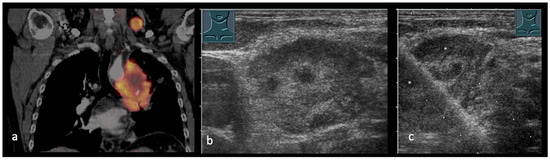

Emerging Role of Transcutaneous Ultrasound in the Diagnostic of Lung Cancer

by Corinna Trenker-Burchert, Marius Dohse, Hajo Findeisen, Andreas Schuler and Christian Görg

Cancers 2025, 17(23), 3873; https://doi.org/10.3390/cancers17233873 - 2 Dec 2025

Lung cancer is one of the most commonly diagnosed malignancies worldwide and continues to be a leading cause of cancer-related mortality. Precise staging is crucial for predicting outcomes and directing treatment decisions. Current international guidelines mainly recommend imaging techniques like CT and PET-CT, [...] Read more.

Lung cancer is one of the most commonly diagnosed malignancies worldwide and continues to be a leading cause of cancer-related mortality. Precise staging is crucial for predicting outcomes and directing treatment decisions. Current international guidelines mainly recommend imaging techniques like CT and PET-CT, with limited references to transcutaneous ultrasound, which is only suggested in particular clinical cases. Ultrasound provides real-time imaging, high resolution in near-field structures, and the ability to assess thoracic wall infiltration, supraclavicular and cervical lymph nodes, pleural effusions, and metastatic lesions. Furthermore, ultrasound-guided biopsies can enable quick and safe histological confirmation of accessible lesions. Based on these advantages and a review of current literature, we propose that integrating ultrasound into staging algorithms could improve diagnostic efficiency, decrease invasive procedures, and support prompt treatment planning. We also highlight the need for further research in this area. Full article

Show Figures

Figure 1